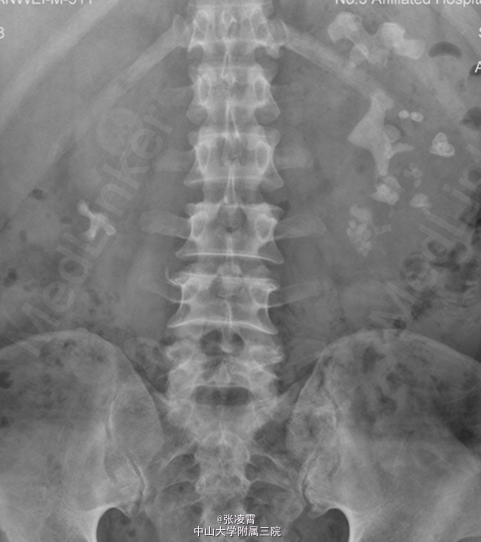

患者男性,51岁,因“左侧腰部胀痛不适20天余”入院。患者20余天前无明显诱因出现左侧腰部胀痛,未伴有发热,寒战,恶心,呕吐,轻度尿频,尿急,尿痛等不适,至柳州市工人医院就诊,尿蛋白+2g/L,潜血阳性,WBC(++),血红蛋白69g/L,肌酐450umol/L;KUB示双肾多发结石,双肾ECT示左肾GFR21.09ml/min,右肾8.84ml/min,考虑为双肾多发结石伴左肾及肾周感染,慢性肾功能不全,尿路感染,肾性贫血,经抗炎等对症治疗后,症状有所缓解。 实验室检查:尿常规:白细胞计数98http://www.medlinker.net/m/casem/12628336计数12.3个/μL,血常规:血红蛋白计数:64g/L。血生化:碳酸氢盐12.0mmol/L,肌酐443μmol/L。凝血四项未见明显异常。 影像学检查:KUB示:双肾多发结石,左侧为著,部分为铸型结石(图1)。外院CTU示:多囊肾,多囊肝,双肾结石(图2、3)。